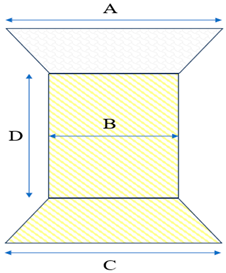

5. Venus P-Valve

- D’Aiello, A.F.; Schianchi, L.; Bevilacqua, F.; Ferrero, P.; Micheletti, A.; Negura, D.G.; Pasqualin, G.; Chessa, M. Holography-guided procedural planning for modifying Venus P-Valve implantation technique in patients with left pulmonary artery stents: A case-series. Front. Cardiovasc. Med. 2024, 11, 1378924. [Google Scholar] [CrossRef]

- Garay, F.; Pan, X.; Zhang, Y.J.; Wang, C.; Springmuller, D. Early experience with the Venus P-Valve for percutaneous pulmonary valve implantation in native outflow tract. Neth. Heart J. 2017, 25, 76–81. [Google Scholar] [CrossRef] [PubMed]

- Morgan, G.; Prachasilchai, P.; Promphan, W.; Rosenthal, E.; Sivakumar, K.; Kappanayil, M.; Sakidjan, I.; Walsh, K.P.; Kenny, D.; Thomson, J.; et al. Medium-term results of percutaneous pulmonary valve implantation using the Venus P-Valve: International experience. EuroIntervention 2019, 14, 1363–1370. [Google Scholar] [CrossRef] [PubMed]

- Jin, Q.; Long, Y.; Zhang, G.; Pan, X.; Chen, M.; Feng, Y.; Liu, J.; Yu, S.; Pan, W.; Zhou, D.; et al. Five-year follow-up after percutaneous pulmonary valve implantation using the Venus P-Valve system for patients with pulmonary regurgitation and an enlarged native right ventricular outflow tract. Catheter. Cardiovasc. Interv. 2024, 103, 359–366. [Google Scholar] [CrossRef]

| Model | Specification | Diameter (mm) | |||

| A | B | C | D | |||

| L28P | P28-25 | 38 | 28 | 38 | 25 | |

| P28-30 | 30 | |||||

| L30P | P30-25 | 40 | 30 | 40 | 25 | |

| P30-30 | 30 | |||||

| L32P | P32-25 | 42 | 32 | 42 | 25 | |

| P32-30 | 30 | |||||

| L34P | P34-25 | 44 | 34 | 44 | 25 | |

| P34-30 | 30 | |||||

| L36P | P36-25 | 46 | 36 | 46 | 25 | |

| P36-30 | 30 | |||||